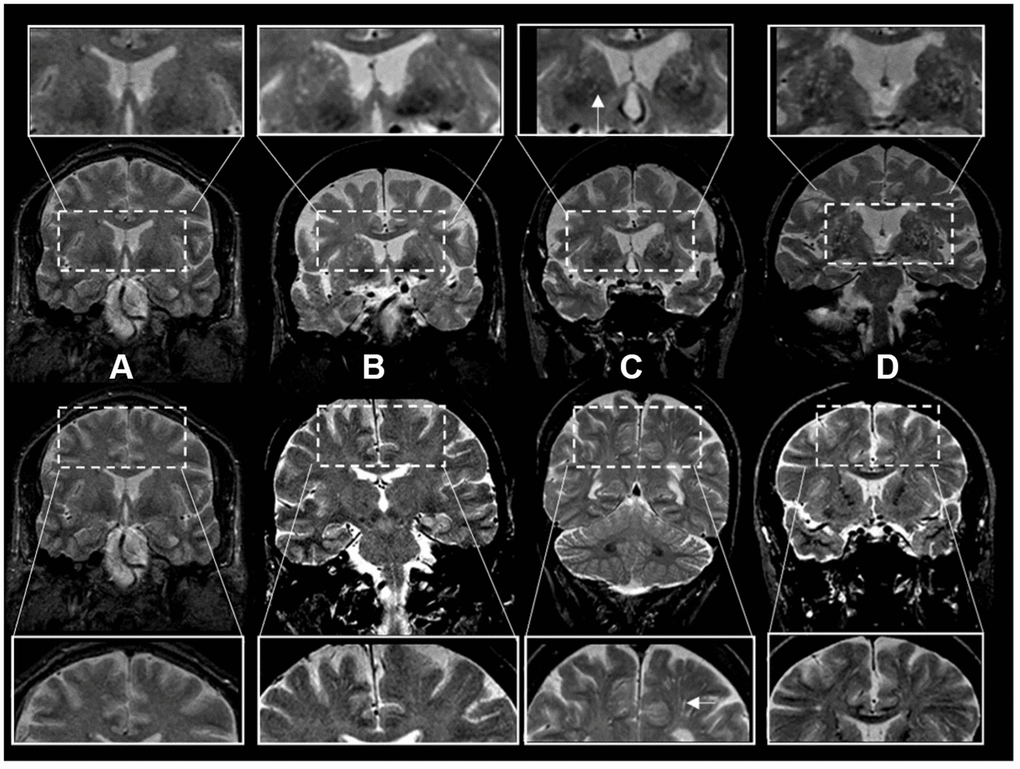

Scans were rated by three investigators (JRR, PP, AS) blinded to the subjects’ demographic and clinical information. T2-weighted axial MRI sequences were the main sequence used for rating ePVS following a validated method [11]. Brain topography of ePVS was classified as centrum semiovale (CSO) and basal ganglia (BG). We also analyzed a mixed group including ePVS in both regions. The burden of ePVS in each region was categorized into grades based on ePVS counts: grade I (1-10), II (11-20), III (20-40) and IV (>40). In a subset of legacy scans from an older dataset, coronal acquisitions were of higher resolution than axial views and were used for ratings (N=1122). For these ratings using coronal views to approximate ratings using axial views we assessed the entire BG region in all slices above the anterior commissure and below the level of the roof of the lateral ventricles. Ratings were based on ePVS burden in the BG bilaterally or in case of presence of large incidental lesions (such as large covert infarcts – without corresponding clinical stroke or TIA event) in the contralesional side. Ratings of the CSO region were performed evaluating the corona radiata, above the level of the lateral ventricles, and subcortical white matter. We categorized burden of ePVS using the same categories as in axial views (Figure 2). In a subset of scans with available high-resolution axial and coronal reconstructions, we compared ePVS ratings in BG and CSO regions based on axial versus coronal sequences. ePVS ratings in BG and CSO were done on 20 scans rated in random order in two separate occasions using axial sequences first, and repeating ratings with the coronal sequence after changing scan order randomly and blinded to the axial ratings. Ratings in axial and coronal sequences were highly correlated with an intraclass correlation (ICC)=0.91.

Figure 2. Enlarged perivascular space burden using ratings in coronal T2-weighted MRI sequences. *Top rows: basal ganglia region. Bottom rows: centrum semiovale region. The inserts represent a closer view. White arrows point to individual examples of enlarged perivascular spaces (panel C inserts). †Grades of ePVS burden are based on T2 weighted coronal views. (A) Grade I (0-10), (B) Grade II (10-20) (C) Grade III (20-40) (D) Grade IV (40+).